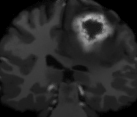

V-C Non-Registered MRI Segmentation Experiments

To demonstrate the robustness of the superpatch structure and the proposed framework, we apply SPM to brain tumor segmentation on multi-modal non-registered Magnetic Resonance Images (MRI). Classical patch-based and multi-atlas structure segmentation methods are based on registered subjects. Consequently, they cannot be efficiently applied in this non-registered context, due to the substantial variation in tumor shape and locations. Superpixels enable to better capture the tumor geometry, thus increasing the segmentation accuracy. Superpixel and supervoxel-based approaches have been applied to tumor segmentation [54]. However, in this work, the neighborhood is not considered and the ANN search is exhaustive, and computed on a large multi-modal histogram descriptor, leading to prohibitive computational time.

SPM can be efficiently applied to tumor segmentation since it quickly finds good correspondences without image registration, and uses the superpixel neighborhood to improve the matching. In this application, the segmentation is computed from a superpixel decomposition [1], then each region (tumor or background) is labeled with SPM.

We present results obtained on the MICCAI multi-modal Brain Tumor Segmentation (BRATS) dataset [49]. This challenging dataset contains real and simulated patient data, with overall poor resolution and large variation of tumor shape and position. For both types, high grade (HG) and low grade (LG) tumors are provided with four modalities: T1, contrast enhanced T1 (T1C), T2, and FLAIR. Overall, there are 20 and 10 real patient data with respectively HG and LG tumors, and 25 images for both HG and LG simulated tumor data. We use the same SPM parameters as in Section V-B, taking a multi-modal histogram, containing the levels of gray intensity on all MRI modalities as descriptor for superpatch matching, and performing the regularization (8) at the pixel scale to compare with pixel-wise ground truths. Each subject is segmented by the remaining of its type in a leave-one-out procedure.

In Fig. 12, we show several tumor segmentation results for all data types.

In Table II, we compare results obtained using different descriptor structures:

patch-based [48], superpixel-based [54],

and superpatch-based (= pixels).

We use the Dice coefficient [55] as evaluation metric,

measuring the overlap between the automatically segmented structure and the ground truth.

The superpixel-based approach

appears very limited since it fails at capturing the tumor context and their location in other images.

Regular patches are also limited in this context, due to the variations in the structure shapes.

Superpatches provide a robust descriptor, since they follow image intensities and capture the superpixel neighborhood,

leading to more accurate segmentation.

These experiments demonstrate that superpatches within the SPM framework provide fast and accurate segmentation results

even on non-registered multi-modal images with poor resolution.